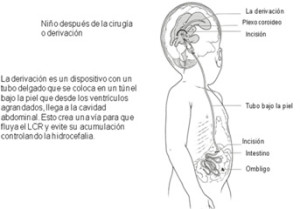

En el 80 por ciento de las personas afectadas por espina bífida, la hidrocefalia sólo se puede tratar insertando un tubo de drenaje llamado “derivación de líquido cefalorraquídeo”.

No existen medicamentos que puedan tratar la hidrocefalia con eficacia. La derivación se coloca debajo de la piel desde la cabeza (ventrículos) hasta la cavidad abdominal, donde el líquido cefalorraquídeo es rápidamente reabsorbido por el cuerpo.

Las derivaciones no son una solución perfecta para el tratamiento de la hidrocefalia, ya que pueden romperse, taparse o infectarse y a veces es necesario reemplazarlas a medida que el niño crece o cuando la derivación falla.

En la mayoría de los casos las derivaciones son necesarias durante toda la vida.

Durante el procedimiento, un neurocirujano coloca la médula espinal y el tejido expuesto dentro del cuerpo del bebé, y los recubre con músculo y piel. Durante la operación de la médula espinal, a veces, se coloca una derivación para controlar la hidrocefalia en el cerebro del bebé.

Sin este tratamiento los bebés pueden sufrir daño cerebral irreversible o morir. Con tratamiento, la capacidad mental del niño se preserva.